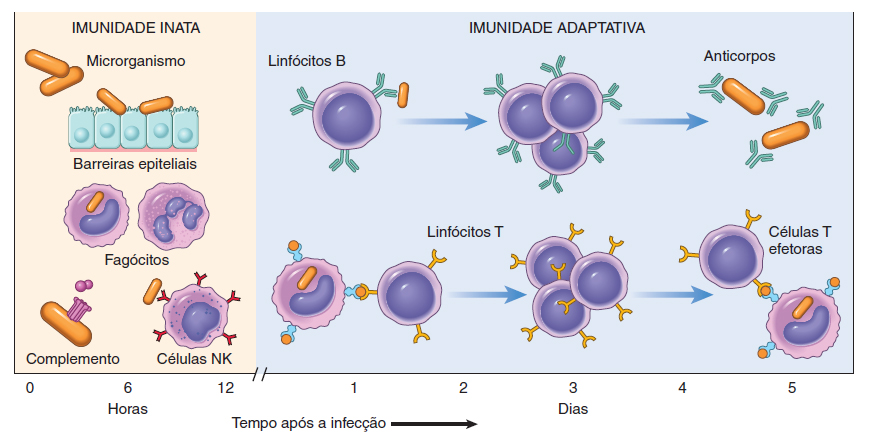

A função imunológica tem sido conceitualmente dividida em imunidade inata e imunidade adaptativa. Assim, uma infeção por um determinado microrganismo provoca em primeiro lugar uma reação imediata, imunidade inata, onde a partir do tecido lesado são segregadas substâncias químicas que vão ajudar a desencadear uma reação de defesa. É representada por barreiras físicas, químicas e biológicas, que impedem a entrada de microrganismos, células fagocitárias (neutrófilos e macrófagos) e células especializadas, célula natural killer (NK).

Esta reação inata, apesar de fundamental, não é específica para o agente infeccioso, não sendo por vezes suficientemente eficaz e para além disso não induz memória imunológica. O segundo tipo de reação, imunidade adaptativa ou adquirida, surge mais tarde, mas é dirigido especificamente para o agente em questão, através da produção de proteínas específicas, anticorpos, que são produzidos pelos linfócitos B e vão reagir com as proteínas (antigénios) do agente infeccioso, impedindo a sua multiplicação e promovendo a sua destruição. Para além disso vão ser ativadas as chamadas células de memória, que vão permitir que o organismo reconheça e produza rapidamente os anticorpos específicos, sempre que entrar novamente em contacto com o agente (Figura 1).

Figura 1 – Imunidade inata e adaptativa.